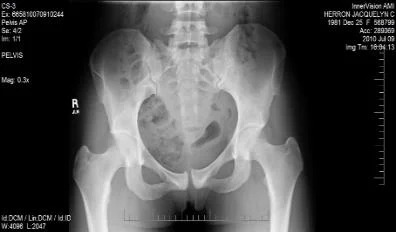

- x-ray of male pelvis and proximal femur, AP view, mature bone fracture in greater trochanter in right side, fracture in neck of femur on left side